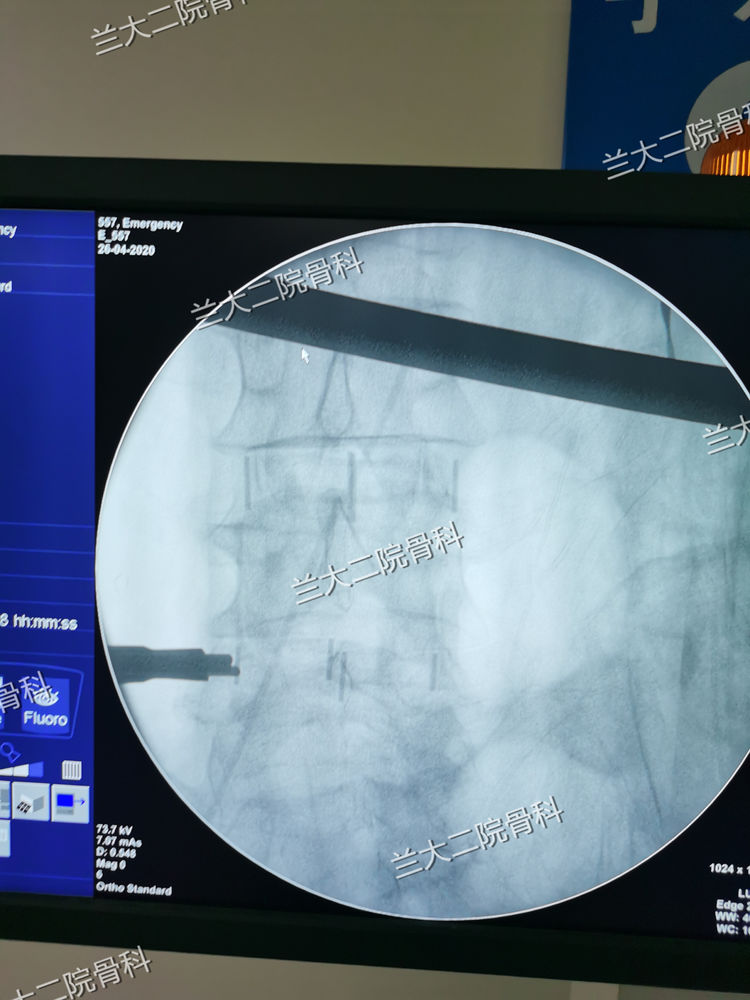

cage植入后脊柱侧弯纠正